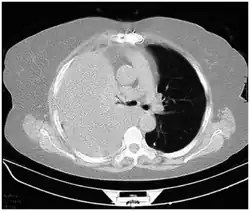

Computed tomography (CT or CAT) scans may be useful for diagnosing retained hemothorax as this form of imaging can detect much smaller amounts of fluid than a plain chest X-ray. However, CT is less used as a primary means of diagnosis within the trauma setting, as these scans require a critically ill person to be transported to a scanner, are slower, and require the subject to remain supine.[23][26]

CT scan of the chest showing a hemothorax caused by warfarin use -